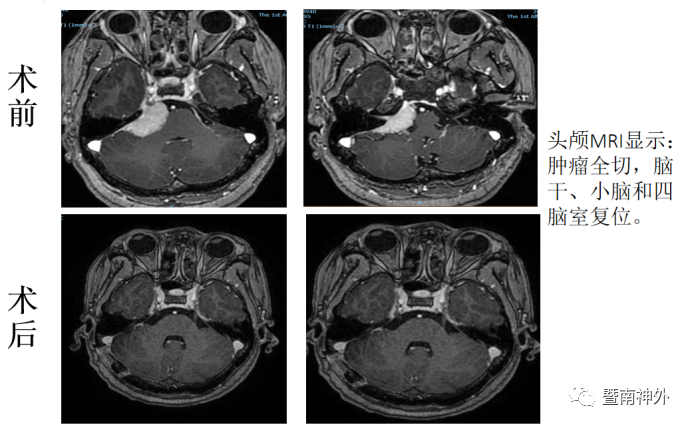

术后半年复查